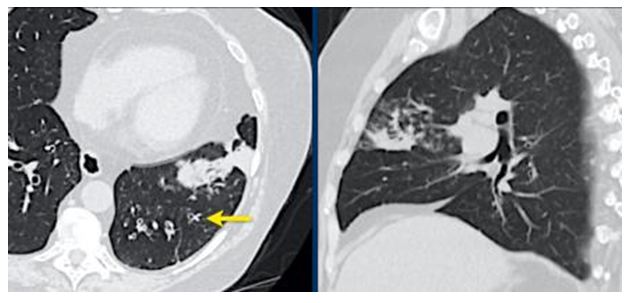

CO-RADS 5: Hình 8 & 9

Hình 8:

Trường hợp 1: Tổn thương đa ổ dạng GGO & đông đặc

Trường hợp 2: Tổn thương đa ổ dạng GGO kèm theo giãn mạch (vòng tròn) & dải băng dưới màng phổi (mũi tên)

Trường hợp 3: Tổn thương GGO & đông đặc cả 2 bên xu hướng vùng sau ngoại vi & nền phổi kèm theo giãn mạch (vòng tròn)